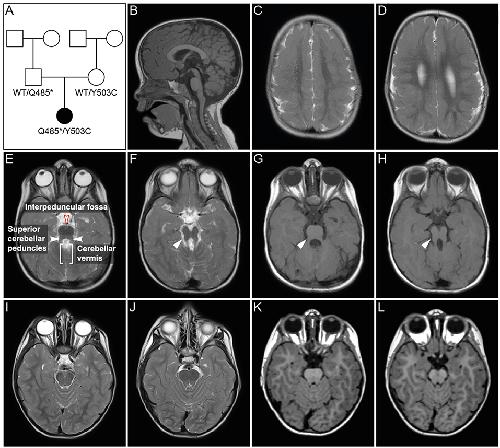

The Frog Xenopus as a Model to Study Joubert Syndrome: The Case of a Human Patient With Compound Heterozygous Variants in PIBF1.,

Ott T,Kaufmann L,Granzow M,Hinderhofer K,Bartram CR,Theiß S,Seitz A,Paramasivam N,Schulz A,Moog U,Blum M,Evers CM,

Front Physiol. January 1, 2019; 10:1664-042X.